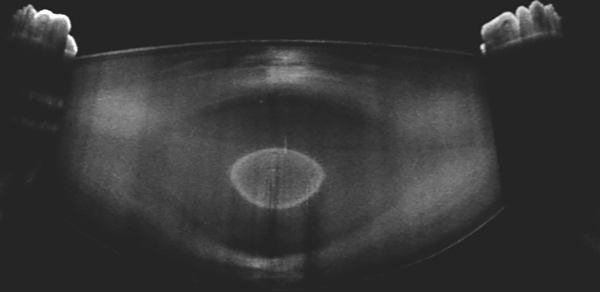

En la imagen obtenida mediante tomografía de coherencia óptica de segmento anterior se puede visualizar la presencia de una opacidad bien delimitada que afecta núcleo fetal y embrionario del cristalino del ojo derecho, compatible con una catarata pulverulenta congénita. Este hallazgo es de herencia autosómica dominante que no afecta significativamente la visión y en este caso es bilateral1.

The image obtained by anterior segment optical coherence tomography shows the presence of a well-defined opacity affecting the fetal and embryonic nucleus of the right eye lens, consistent with congenital pulverulent cataract. This finding is inherited in an autosomal dominant pattern, which does not significantly affect vision and in this case is bilateral1.